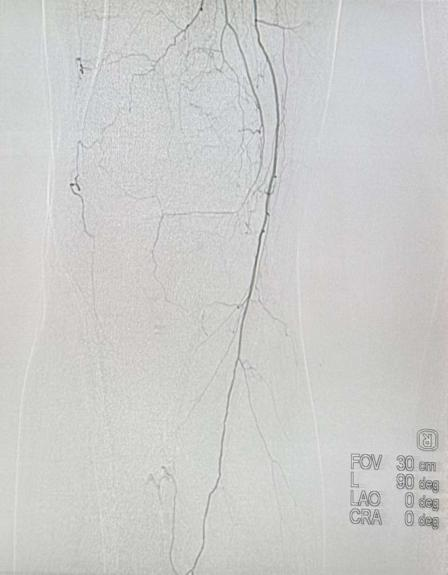

手术在局部麻醉下通过大腿根部微小穿刺进行。术中血管造影清晰显示股浅动脉及腘动脉内长段血栓栓塞,血流中断,侧枝血管供应小腿。

导丝通过闭塞段后,引入旋切导管——这套系统的核心优势在于通过高速旋转的刀头,将血栓粉碎并同步负压吸出体外,实现“一边清除血栓、一边恢复血流”的即时效果,无需长时间溶栓等待,也大幅减少了溶栓药物用量,对于高龄、基础病多的患者来说特别安全。